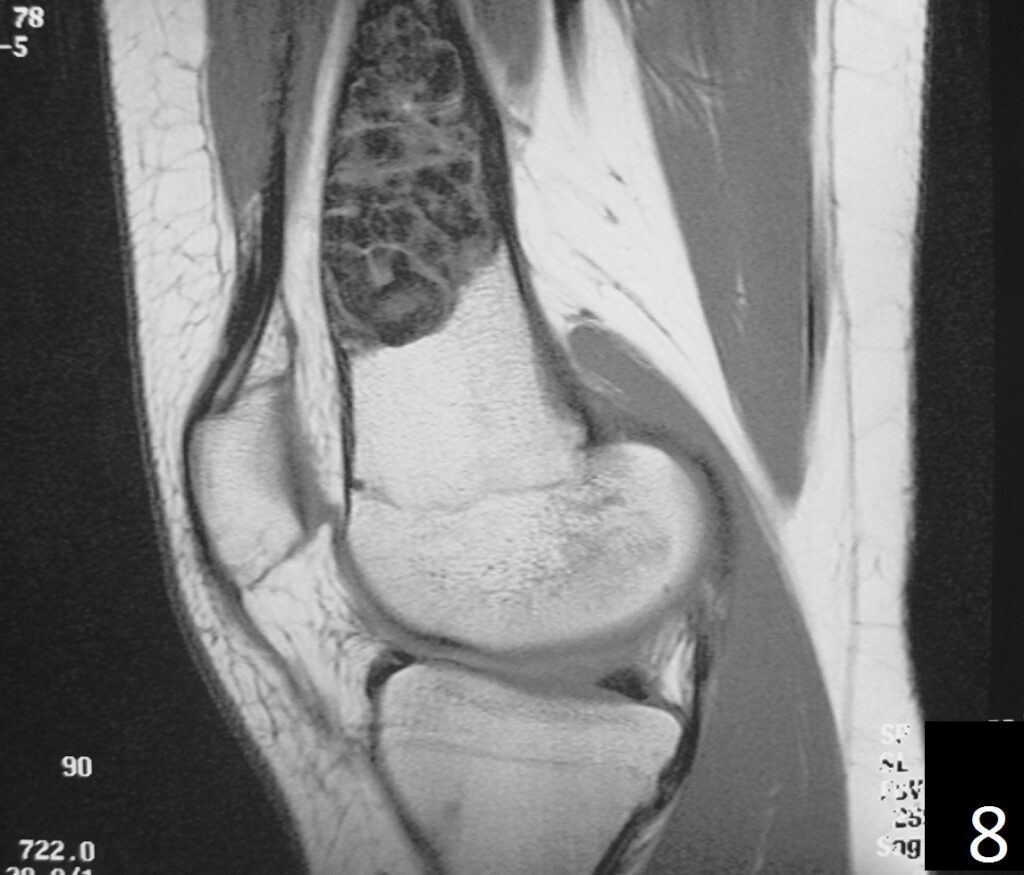

MRI

• Low- signal on T1 (Fig. 8)

Fig. 8

Fig. 9

Fig. 6-9: Sagittal T1 (Fig. 6) and T2 (Fig. 7) MRI of the knee demonstrates a fibrous cortical defect. Axial T1W (Fig. 8) and T2W (Fig. 9) show a heterogeneous lesion on distal femur, compatible with nonossifying fibroma.